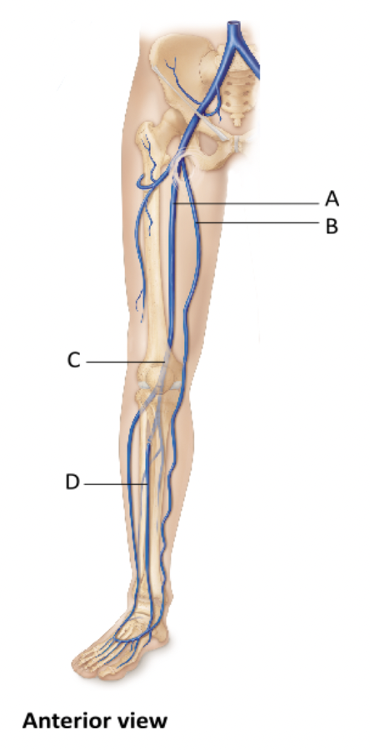

Name the vein at A.

- femoral vein

- small saphenous vein

- fibular vein

- external iliac vein

femoral vein

Ex.

The femoral vein is the largest vein draining the lower extremity. It unites with other veins to form the external iliac vein.